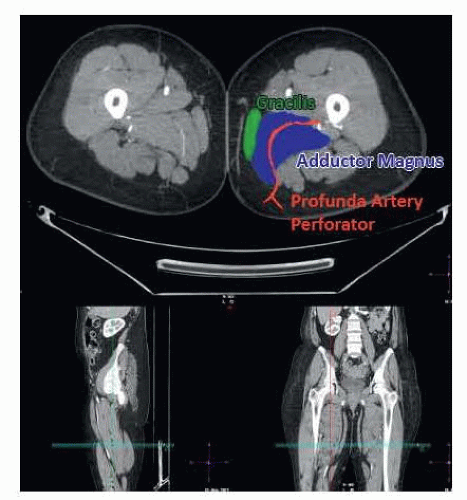

Perforators should be described as they exit the deep muscular fascia and described based on location in an x–y axis. The gluteal fold will be set as zero on the y-axis, and the posterior border of the gracilis will be set as zero on the x-axis (FIG 3).

FIG 3 • CTA of the lower extremity identifying the location of the profunda artery perforator behind the gracilis traversing the adductor magnus toward the profunda femoris artery.